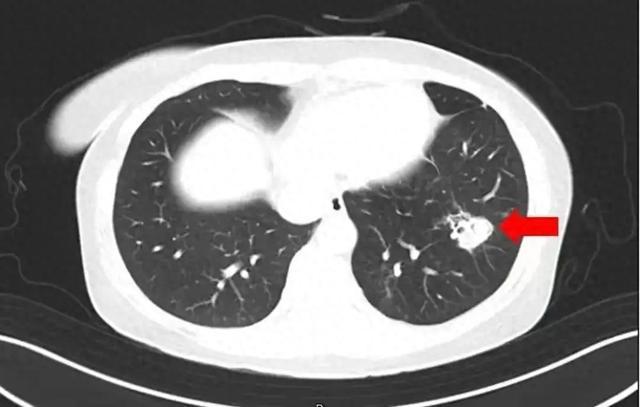

图片图源:健康杭州

为进一步确诊病情,医生为她进行纤维支气管镜检查及肺泡灌洗液病原体检测,果然发现气道壁上有大量白色菌斑,化验后确认是曲霉菌。